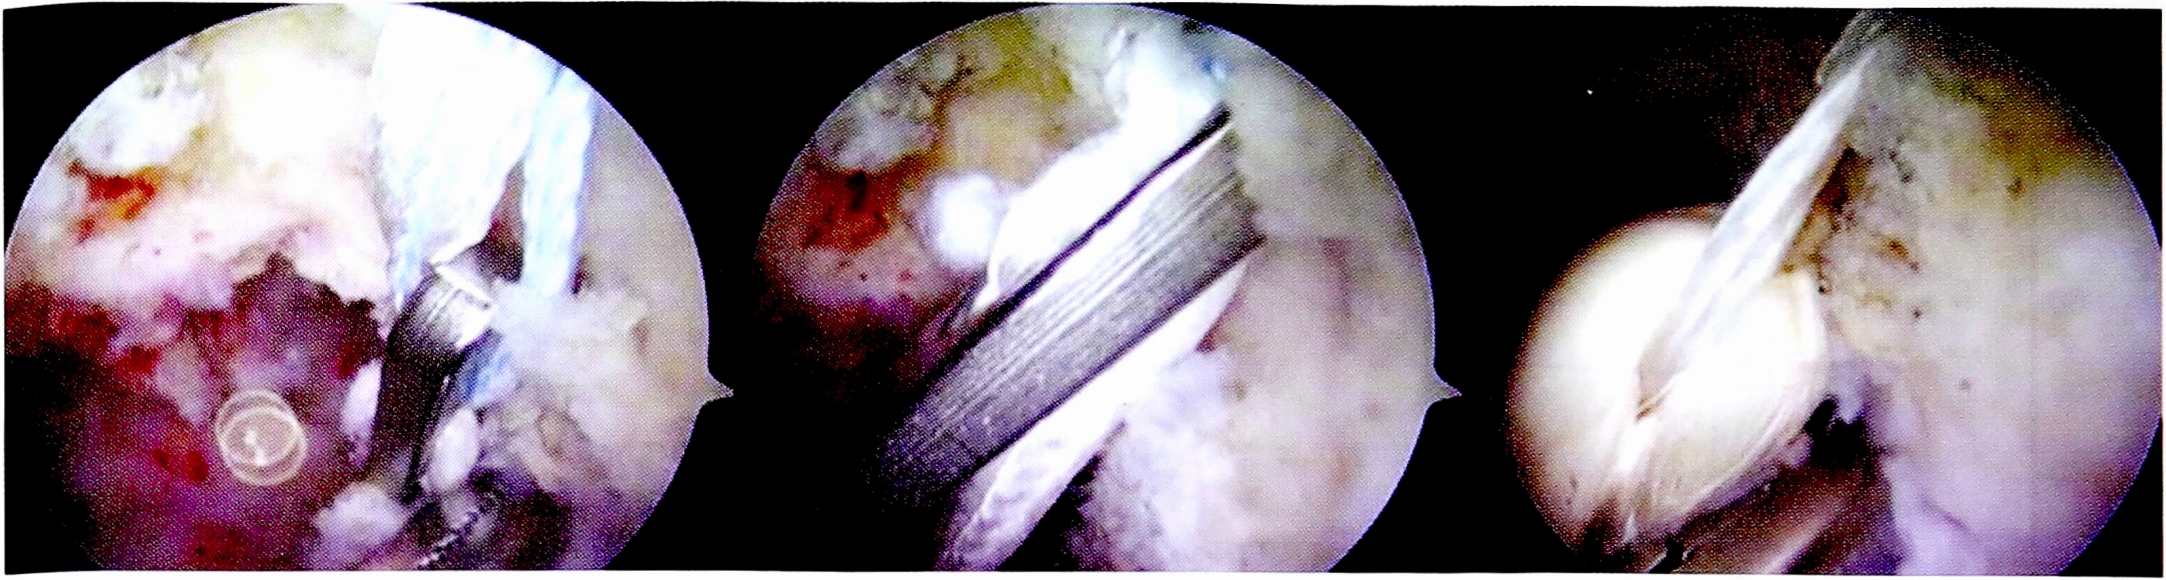

После проведения и фиксации на бедренной кости трансплантата ЗКС формировались костные тоннели для пластики ПКС. Использовались стандартная транстибиальная методика и набор направителей для ее выполнения (рис. 7).

Рис. 7. Артроскопическая картина основных этапов пластики ПКС.

Fig. 7. Main stages of ACL plasty.

Таким образом, костные тоннели в большеберцовой кости проводились через разноименные мыщелки: латеральный для ЗКС и медиальный для ПКС.

Следует отметить необходимость соблюдения строгой последовательности фиксации аллотрансплантатов в костных тоннелях. Авторами рекомендуется первым этапом выполнять натяжение и фиксацию в каналах трансплантата ЗКС, затем — трансплантата ПКС. Такая последовательность позволяет максимально вывести голень из заднего подвывиха. Последним этапом производится дополнительное натяжение фиксированных трансплантатов за счет самозатягивающихся петель фиксаторов в бедренных каналах.